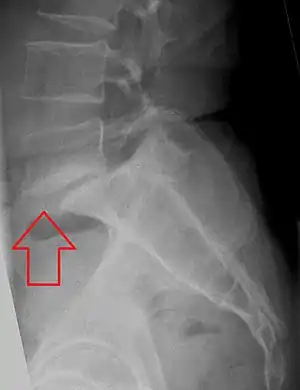

X-ray of measurement of spondylolisthesis at the lumbosacral joint, being 25% in this example.

Classification by degree of the slippage, as measured as percentage of the width of the vertebral body:[36] Grade I spondylolisthesis accounts for approximately 75% of cases.[23]

- Grade I: 0–25%

- Grade II: 25- 50%

- Grade III: 50–75%

- Grade IV: 75–100%

- Grade V: greater than 100%